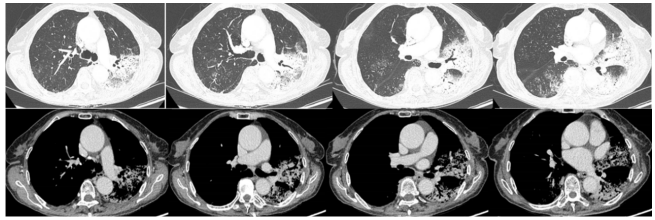

- 胸部CT(2024-06-13):左肺舌段和左下叶斑片实变影,右肺下叶可见斑片状阴影,肺中叶散在病变(图1)。

经过上述治疗,患者WBC、CRP、LDH、PCT均逐渐下降,肌酐正常。8月10日检查:WBC 9.1×109/L,CRP 6.8 mg/L,PCT 0.04 ng/ml,LDH 406 U/L。8月3-10日期间,患者心率持续变快,需要两种血管活性药物控制血压,无法进行俯卧位通气。ECMO上机前,患者右肺渗出性病变明显加重(图3)。

8月11日呼吸机吸氧浓度40%,ECMO气浓度约为80%,持续3天,激素减量氧合恶化,因心脏问题不能俯卧位通气(心率快,应用艾司洛尔及胺碘酮控制心室率)。气道分泌物不多,炎症指标正常。心脏问题,快速性心律失常,请心内科专家会诊,考虑舒张功能障碍,建议盐酸地尔硫卓联合胺碘酮控制心室率,血压低考虑可能血管张力问题,为减轻去甲肾上腺素对心脏的刺激,调整间羟胺维持血压。6月26日用抗肿瘤靶向药物后,8月1日肺部CT,双肺病变明显加重,肿瘤进展还是感染诱发?或是肿瘤靶向药物引起的免疫相关性肺损伤?下一步怎么办?肿瘤靶向药物还能用吗?8月11日请詹庆元教授会诊,考虑肿瘤靶向药物引起间质性肺炎可能性大,甲强龙80 mg q12h;心内科建议倍他乐克6.25 mg q12h口服联合盐酸地尔硫卓控制心室率;间羟胺替换去甲肾上腺素。8月12日心率65~85次/分,俯卧位8小时,白天ECMO 80%下调60%。患者氧合持续好转,随着病情好转,抗生素降阶梯治疗。8月13日,BALF涂片发现大量白细胞,以及多种形态阴性杆菌,像洋葱伯克霍尔德菌和伊丽莎白菌。8月14日,tNGS结果回报按蚊伊丽莎白菌、洋葱伯克霍尔德菌和脓肿分枝杆菌。据此调整抗感染药物:磺胺2片tid,多黏菌素E,美罗培南,利奈唑胺,伏立康唑。8月20日撤离ECMO。8月21日,病原学提示脓肿分枝杆菌进行性增多,加用左氧氟沙星。8月26-28日尝试甲强龙减量(60 mg→40 mg),患者再次再次出现氧合变化,未能成功转换为无创通气,有创通气PS降至8 cmH2O,PEEP 5 cmH2O。复查胸部CT,发现右肺渗出性病变再次出现。8月29-30日,甲强龙剂量调整为80 mg。8月31至9月3日,甲强龙剂量调整为60 mg。8月27日复测tNGS,回报木糖氧化无色杆菌(序列数47605),人类疱疹病毒1型(序列数176998),按蚊伊丽莎白菌、洋葱伯克霍尔德菌和脓肿分枝杆菌序列数较前减少。细菌室回报木糖氧化无色杆菌。患者出现了一些不良反应,包括骨髓抑制,纤维蛋白原、血小板、血红蛋白、白细胞、淋巴细胞数都在降低。考虑可能是磺胺药物和利奈唑胺引起,所以停用这两种药物。调整抗感染药物:阿米卡星雾化,左氧氟沙星,多西环素,伏立康唑,阿昔洛韦。之后由于不良反应,8月31日停用了左氧氟沙星和多西环素。9月3日查血,患者血小板升高。如下图所示,6月15日为抗肿瘤药物使用前,8月1日为抗肿瘤药物使用后,8月19日第一次复查CT,激素减量后,8月29日再次复查CT,右肺渗出性病变较前明显增多(图4)。

图4 患者影像学变化

患者存在两大问题,一是撤机困难,二是肌无力。后续复查影像学发现右肺斑片渗出逐渐好转,积极进行四肢肌力和膈肌的康复治疗。